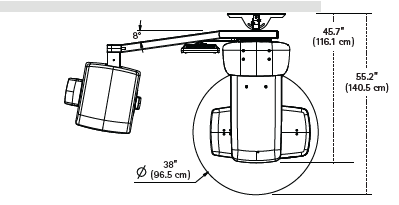

X-Ray System Incudes: